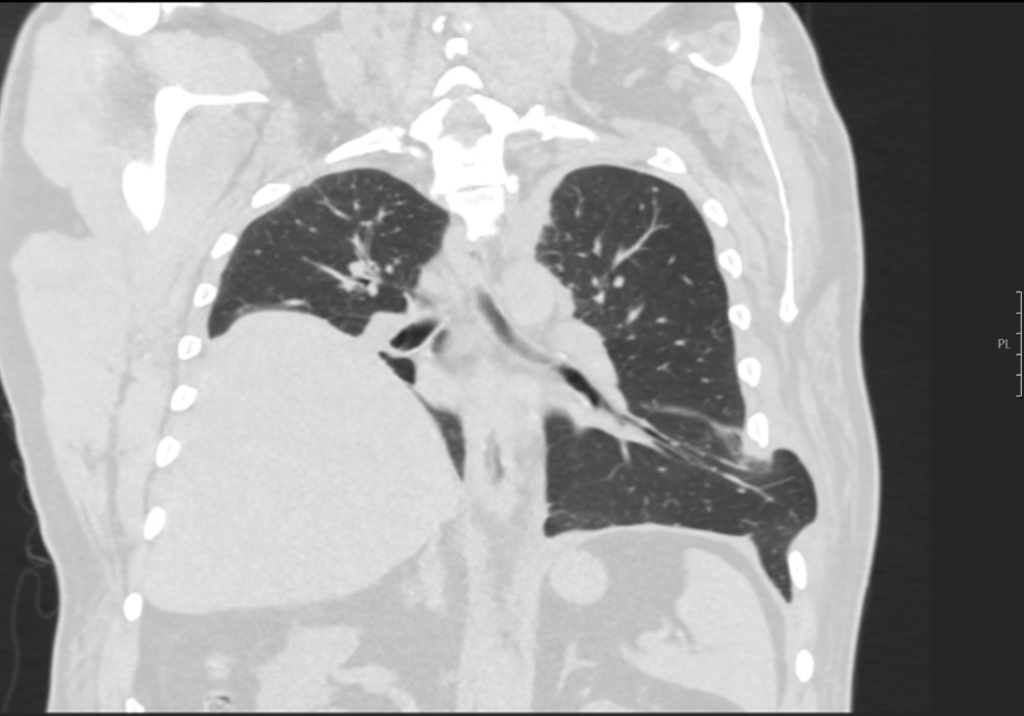

Een 66-jarige man komt bij de huisarts met hoestklachten en een hematoom in de linker flank. De voorgeschiedenis vermeldt onder andere astma bronchiale en een hoogstand van de rechter diafragmahelft. Lichamelijk onderzoek laat een zwelling zien ter hoogte de linker scapula. Deze zwelling fluctueert in grootte tijdens het hoesten. Er wordt een CT-scan gemaakt.